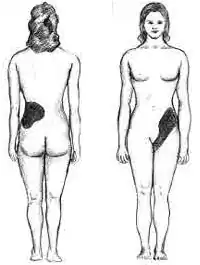

-

Abscess around both kidneys[24]

-

Abscess around both kidneys[24]